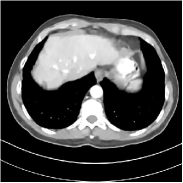

Refer to caption FBPRMSE = 194.09 HURefer to caption FBPRMSE = 194.09 HURefer to caption PWLS-ULTRARMSE = 43.40 HURefer to caption PWLS-ULTRARMSE = 43.40 HU

Refer to caption FBPConvNetRMSE = 34.24 HURefer to caption FBPConvNetRMSE = 34.24 HURefer to caption SUPER-FCN-DataTermRMSE = 31.21 HURefer to caption SUPER-FCN-DataTermRMSE = 31.21 HU

Refer to caption SUPER-FCN-ULTRARMSE = 28.82 HURefer to caption SUPER-FCN-ULTRARMSE = 28.82 HURefer to caption ReferenceRefer to caption Reference

Figure 5: Reconstructed images of slice 150 of patient L192 using of FBP, PWLS-ULTRA, FBPConvNet, SUPER-FCN-DataTerm, and SUPER-FCN-ULTRA, respectively, shown along with the reference.

Fig. 5 shows reconstructions using FBPConvNet, SUPER-FCN-DataTerm (i.e., β=μ=0𝛽𝜇0\beta=\mu=0), PWLS-ULTRA, and SUPER-FCN-ULTRA, respectively. For SUPER-FCN-DataTerm, when optimizing the data-fidelity term, we start with the deep network’s output and ran 5 iterations for the data-fidelity term to avoid overfitting to the analytical FBP images. In Fig. 5, obviously, FBPConvNet significantly suppresses noise and artifacts compared to PWLS-ULTRA, but it also over-smooths many details (e.g., features in the zoom-in box) in the reconstruction. SUPER-FCN-DataTerm, by enforcing data consistency, helps reduce overfitting issues and reconstructs image details and tissue boundaries better compared to the standalone FBPConvNet. Our SUPER-FCN-ULTRA method, however, exploits richer prior information (via the union of learned sparsifying transforms) and explicit network regularizer and outperforms the SUPER-FCN-DataTerm approach. Additional such comparisons for other selected test slices are included in the supplement (Fig. 15).